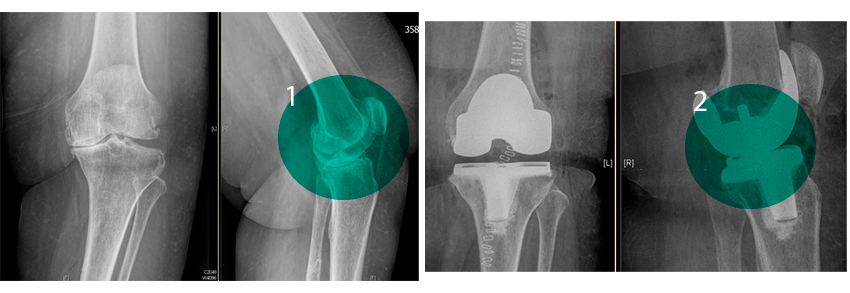

Ergebnis einer Knie-Totalendoprothese:

Vorher und Nachher